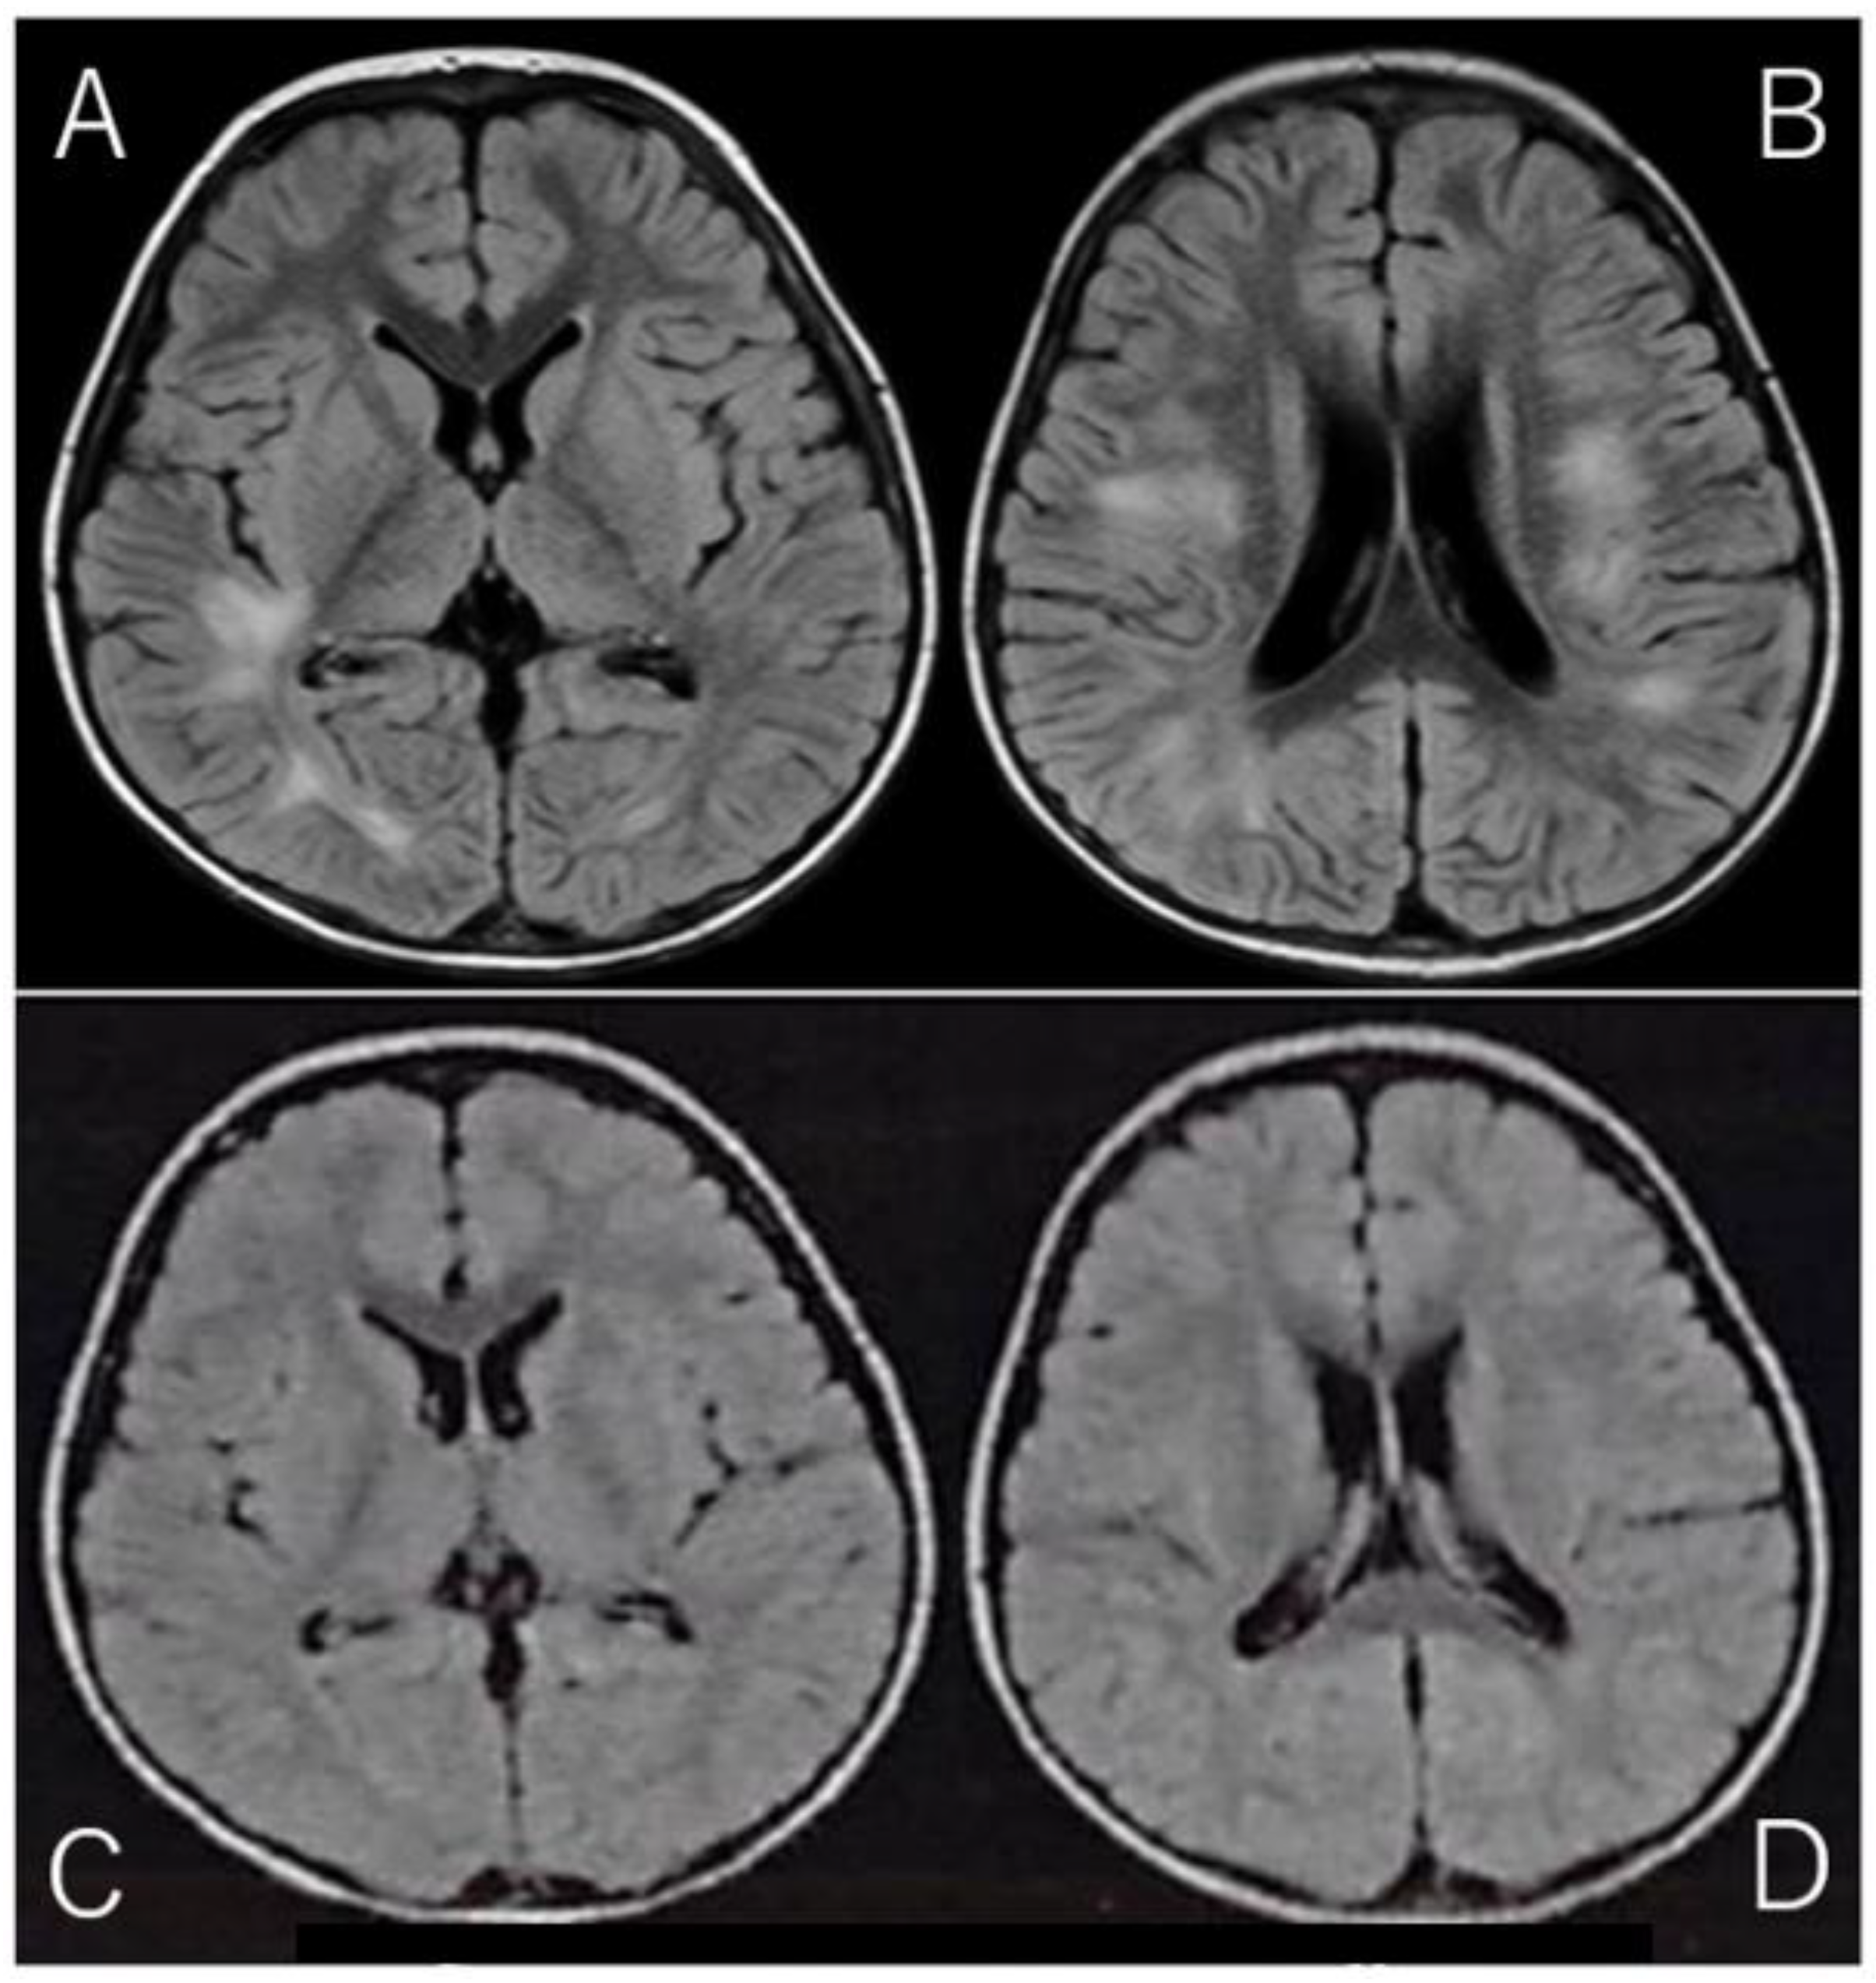

2. Case Report